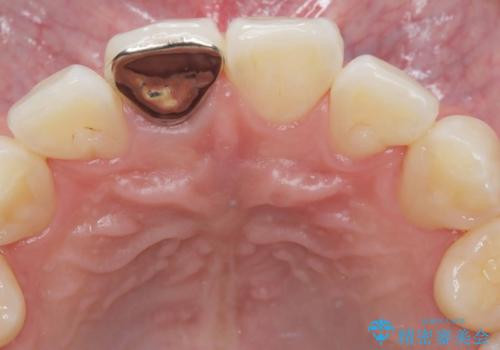

- 前歯の見た目が気になるを主訴に来院された患者様です。

根管の充填物も不十分だったため根管治療からやり直しオールセラミッククラウンで治療を行いました。

根管の中が空洞のままで被せ物と歯のきわも合っておらず適合が悪い状態でした。根尖部付近にはパーフォレーションリペア修復の痕がありました。バイオシーシーラーを使用しシングルポイント法で充填しました。空洞があると細菌が増える環境になってしまうので、根管治療からやり直し、緊密に充填しました。被せ物の見た目も大変満足していただけました。